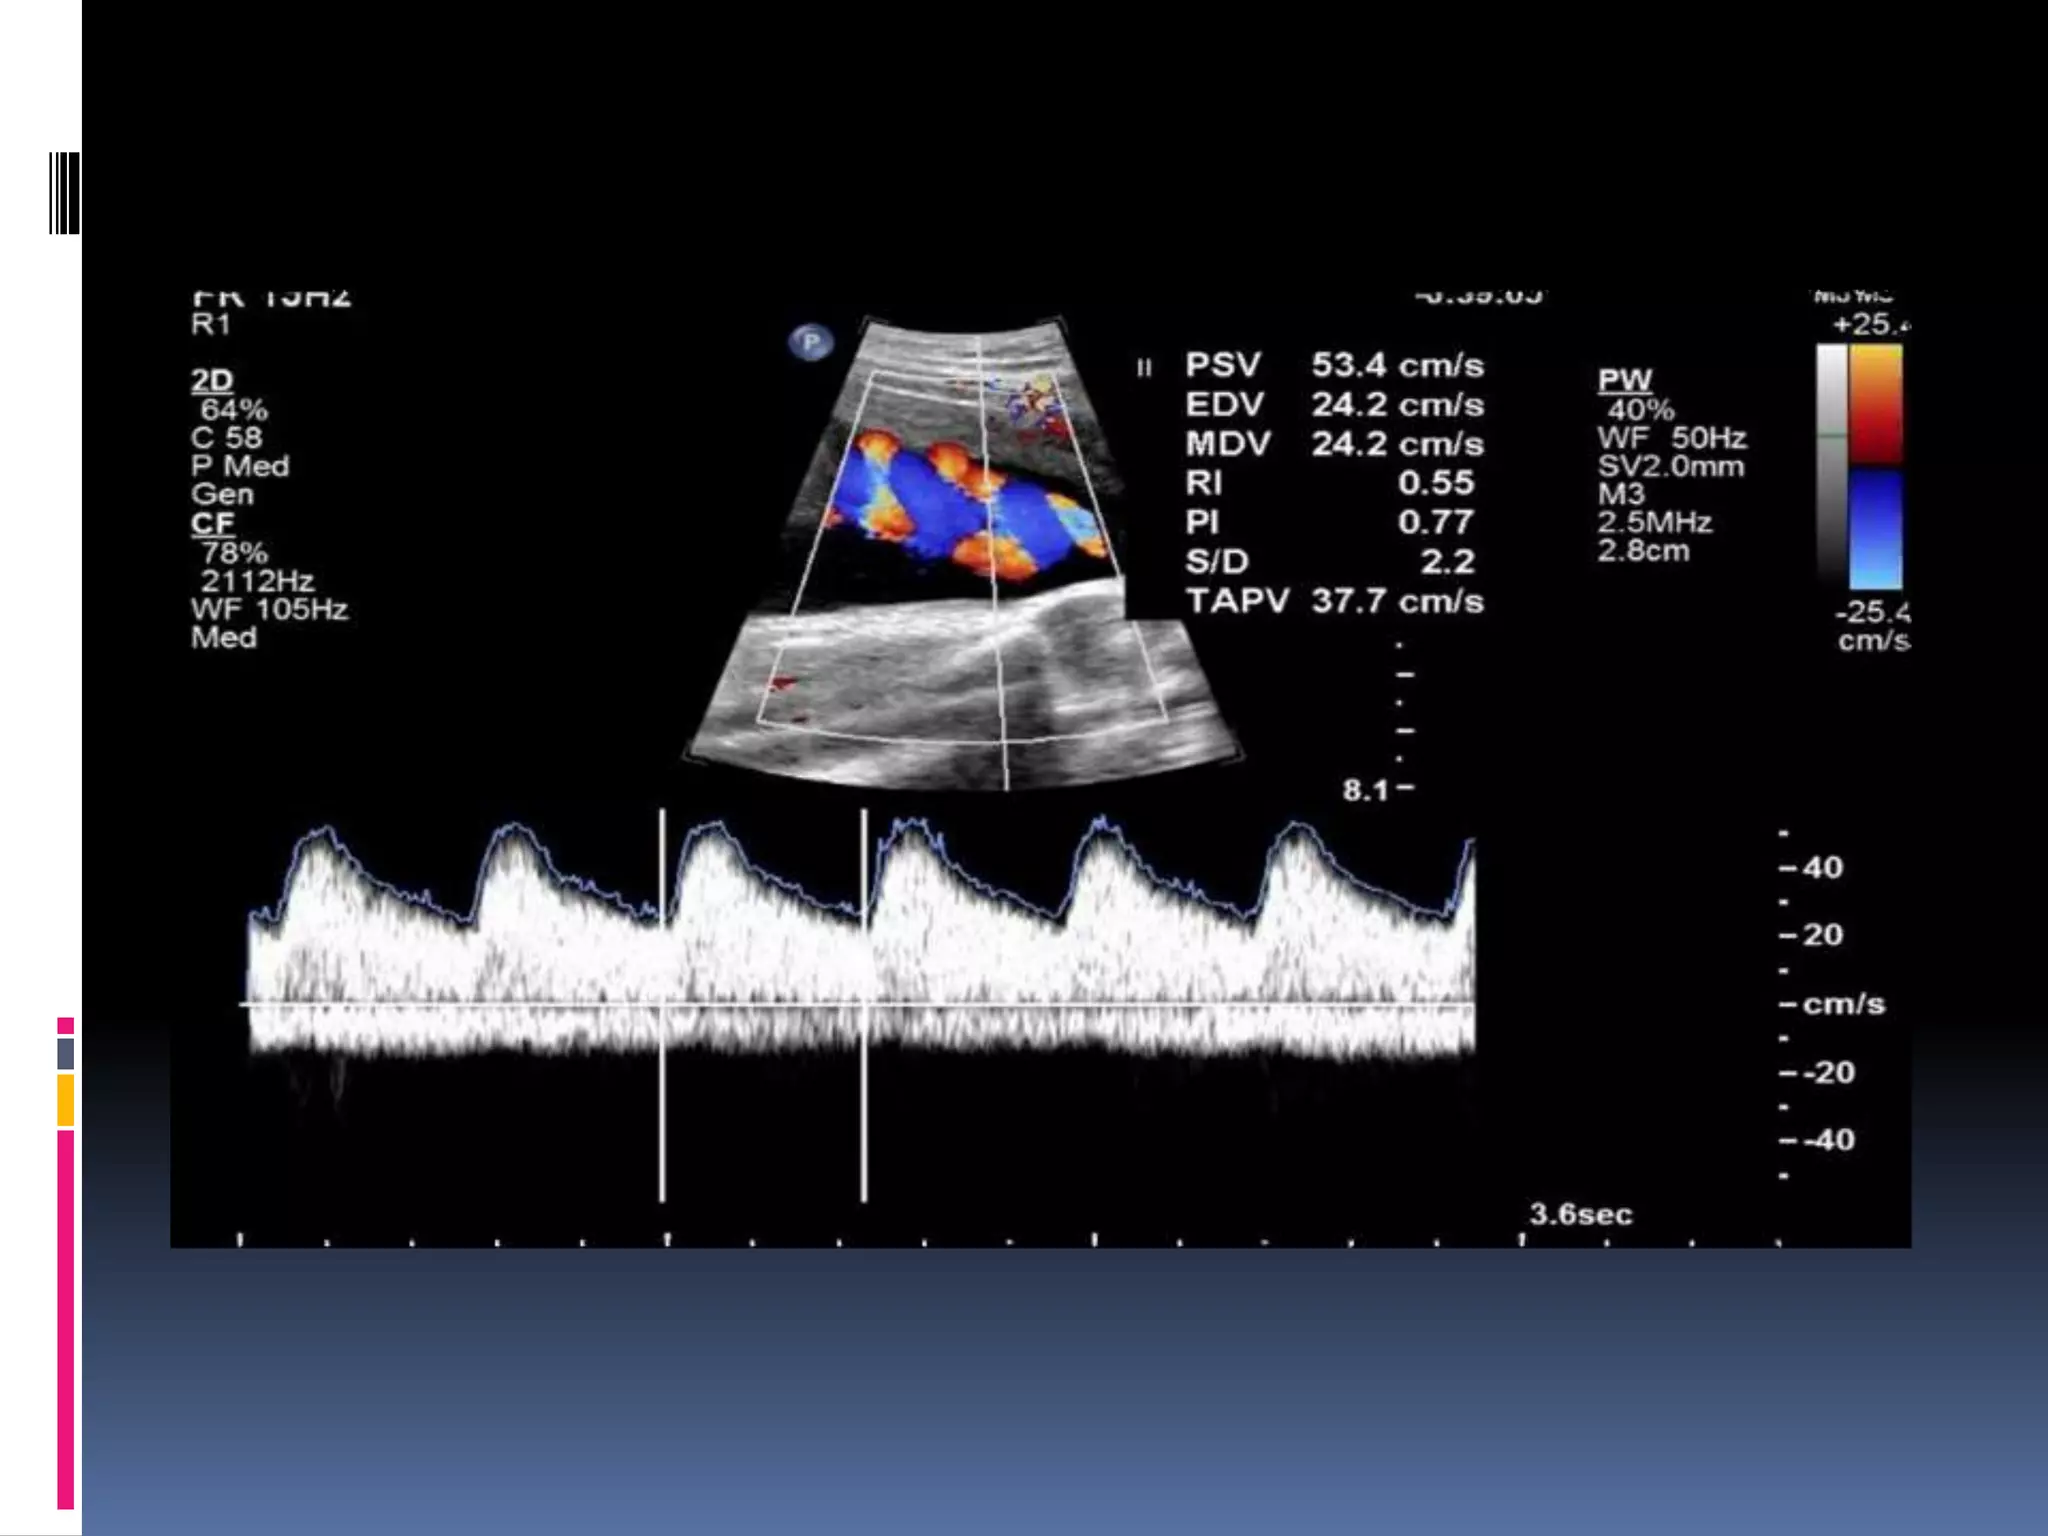

fetal aorta

Thoracic descending aorta in

healthy fetus

IUGR IN 27 WEEK descending

aorta